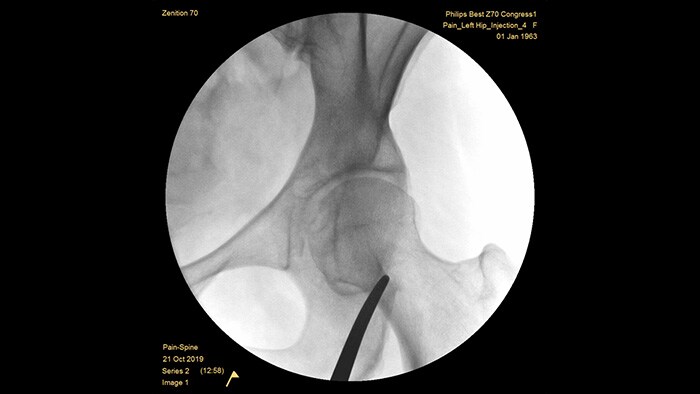

Системы с плоскими детекторами четвертого поколения обеспечивают исключительную четкость визуализации плотных и сложных анатомических структур. Компактная форма экономит пространство и обеспечивает удобство позиционирования при лечении хронической боли в суставах. Функция Position Memory2 увеличивает возможность позиционирования с первого раза и сокращает число вспомогательных ориентировочных изображений3 для эффективного рабочего процесса при лечении болевого синдрома. Система Zenition 70 доступна с детекторами двух размеров: плоский детектор 26x26 см обеспечивает обширный охват анатомической области, а плоский детектор 21x21 см оставляет достаточно места для работы вокруг пациента.

Оптимальная глубина полностью уравновешенной С-дуги обеспечивает достаточно места для размещения вокруг пациентов с лишним весом и позволяет получать изображения поясничного отдела позвоночника и тазобедренного сустава. Она поддерживает позиционирование над столом даже для столов с большим основанием.